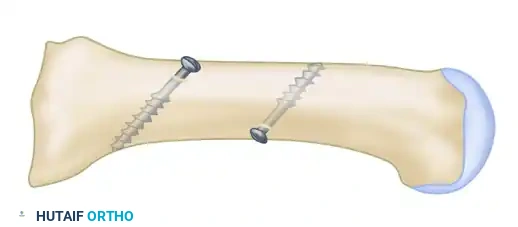

Phase 4: Reduction and Internal Fixation

Achieving and holding the correct multiplanar reduction is the most technically demanding portion of the procedure.

- Mobilization: Insert a Freer elevator into the osteotomy site to verify that no periosteal hinges remain medially or laterally. The fragment must be completely mobile.

- Displacement and Rotation:

- Displace the proximal fragment medially and hold it securely with a Freer elevator.

- Simultaneously, rotate the distal fragment laterally around the osteotomy site (typically requiring 2 to 4 mm of lateral translation/rotation).

- Pitfall Avoidance: Strictly prevent the distal fragment from sliding dorsally (which causes transfer metatarsalgia) or plantarward.

- Fixation: While the surgeon holds the exact reduction, an assistant completes the fixation.

- Place a centering device ("golf tee" or "mushroom" guide) into the pre-drilled 3.5-mm glide hole.

- Drill the proximal fragment with a 2.0-mm or 2.5-mm drill bit.

- Tap the proximal fragment with a 4.0-mm tap.

- Insert a 4.0-mm fully threaded cancellous screw (typically 26 mm in length).